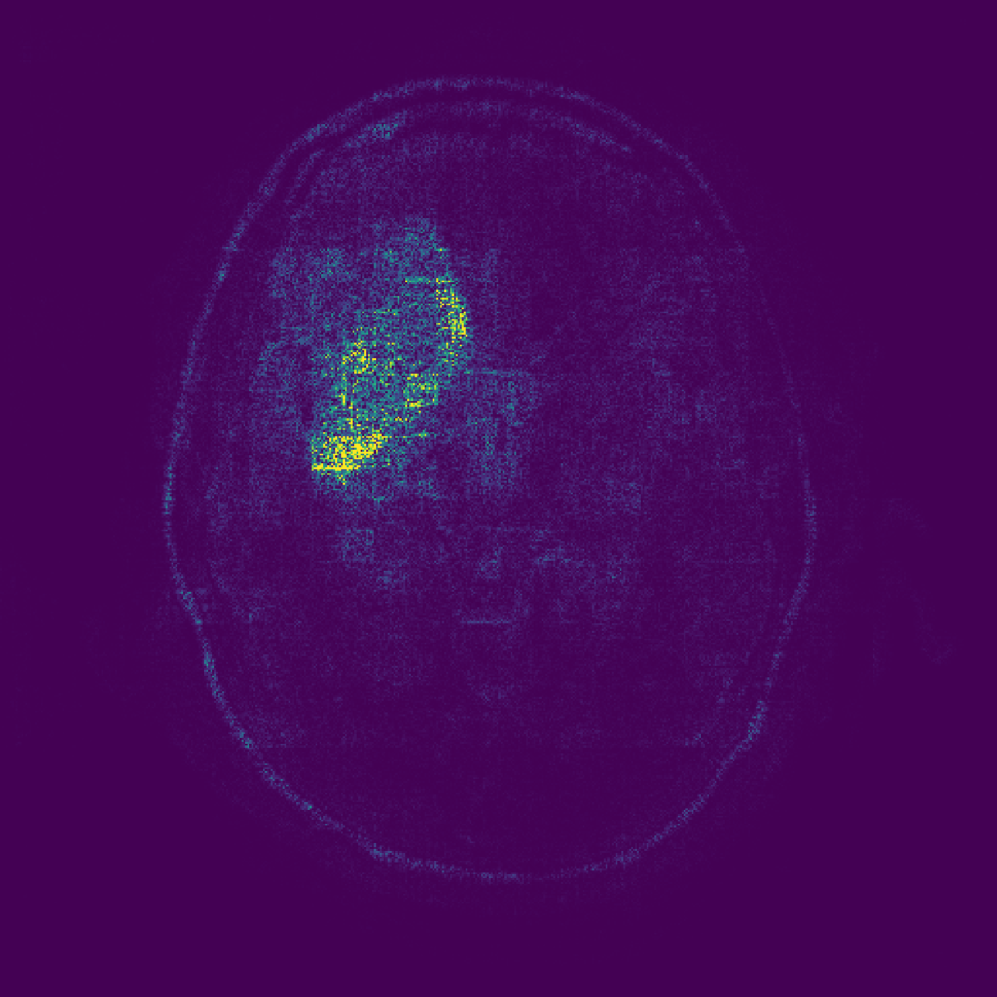

Figure 3: Examples of attributions obtained using different baselines. Typical colormaps for the respective domains are used (i.e. blue\rightarrowred for the Manometry data set and black\rightarrowwhite for the other two). For EG and EG (CF) we show the mean of the sampled baselines, providing a single representation for illustration purposes.

We evaluate the baselines on three medical data sets containing class labels and segmentation masks for pathological region localization. Images are resized to 512×512512\times 512 and normalized to [0,1][0,1]. Evaluation is based on correctly classified, pathological test samples with available segmentation masks. Dataset sizes are detailed in Table 5. Train/test splits are either predefined (Chest X-ray, Brain MRI) or randomly selected (Manometry). For a qualitative impression, Figure 5 shows an example input from each data set with corresponding attribution maps for the various baselines we compare.

Brain MRI  The data set333Available at: https://www.kaggle.com/datasets/mateuszbuda/lgg-mri-segmentation/data comprises brain MRIs for tumor classification and segmentation tasks Buda et al. (2019). The data set contains two classes, comprising normal and pathological samples, with the tumors mostly visible as bright regions due to contrast agent.